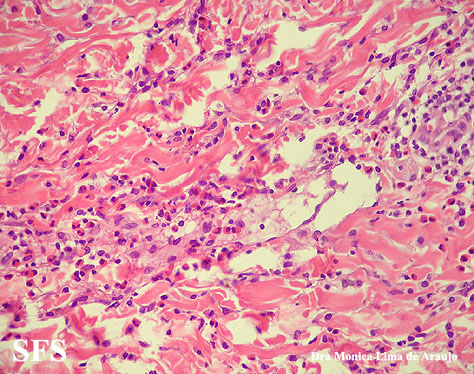

eosinophilic annular erythema